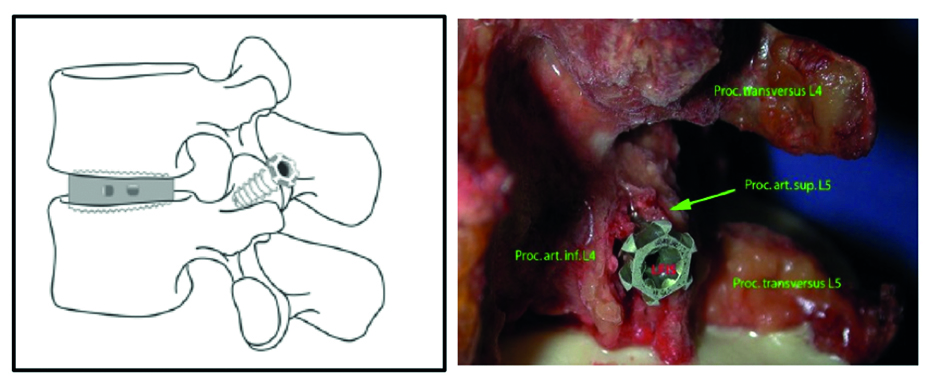

A 40-year-old man 5 years after ALIF L4-L5 using SynFix with axial low back pain. The CT scan shows locked pseudarthrosis (Fig 17). Nonoperative treatment failed. The treatment option was bilateral Facet Wedge at L4-L5.

A less invasive approach was used with Insight Retractor using the bilateral Facet Wedge. No bone graft. X-ray follow-up after 3 months and CT assessment after 6 months (Fig 18-19).